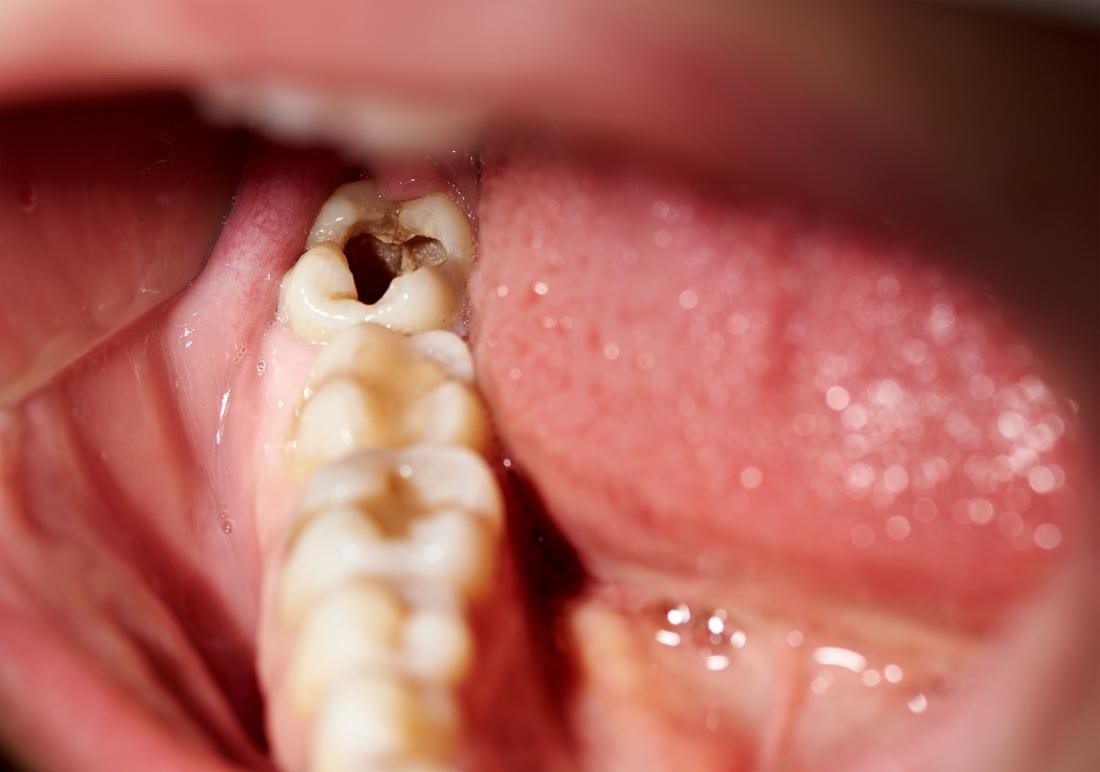

A rotten tooth is one that is severely decayed. The decay, also known as dental caries or a tooth cavity, begins with the breakdown of the tooth enamel. Plaque builds up and combines with bacteria to break down the enamel. Once the enamel has broken down, cavities develop. If you fail to treat your cavities, they will get worse. Dental caries is an open invitation to bacteria to further invade your teeth and beyond.

Visually, you might first notice discoloration as the enamel deteriorates followed by tiny holes in your teeth. You will also see dark spots as the decay becomes more apparent. As the decay gets worse, the toothaches will become unbearable, your teeth can crack, pieces of your teeth can break off, or a tooth can completely break at the gum line. You will start having trouble eating and may lose weight. It is possible you will lose important nutrients that are critical to your health. The symptoms of a rotten tooth will grow more severe as time goes by. You are more likely to notice this kind of symptom in a rotten back tooth or rotten bottom teeth. In comparison, rotten front teeth are relatively rare.

Tooth Decay Stages

There are three tooth decay stages. Early-stage decay is little more than an initial breakdown in the tooth enamel. There might be very tiny cavities, but early tooth decay stages can usually be reversed. Advanced tooth decay stages show significant cavities. At this stage, dental caries has gone further than just the enamel but have not yet reached the pulp of the tooth. Very advanced tooth decay stages show dental caries in the pulp of the tooth.

Very Advanced Stage Treatment Options

When decay reaches the inner pulp of your permanently damaged tooth, a root canal may be the last resort to save your tooth. Your dentist will need to remove the affected pulp and replace it with filling material. It is common practice to place medicine in the tooth beneath the filling material to fight any remaining bacteria. If the tooth is decayed beyond restoration, your dentist will need to extract the tooth. X-rays are used t0o confirm the need for root canals.